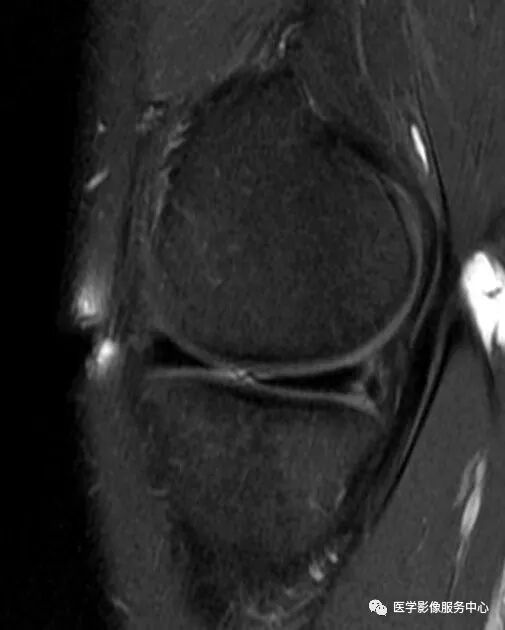

常见于外侧半月板桶柄样撕裂。半月板后角消失,离断的半月板后角向前方移位,位于前角后方,中间填充关节液,形成半月板前角假性肥大。

半月板前角假性肥大举例

黑色箭头所指为半月板前角,白色箭头所指为撕裂的半月板向前移位